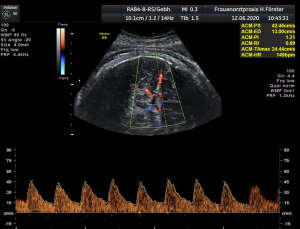

Gynäkologische Grundversorgung Frauenärztliche Krebsfrüherkennungsuntersuchung Nachsorge und supportive Therapie bei bösartigen gynäkologischen Tumoren Impfungen Brustultraschall Ultraschalluntersuchung der weiblichen Genitalorgane Psychosomatische Grundversorgung Chlamydienscreening FOB-Test (früher Hämoccult) Kontrazeption Geburtshilfliche Grundversorgung Geburtshilflicher Basisultraschall Erweiterter Basisultraschall (Organscreening) zw, 18-22.SSW Doppler/Duplexsonografie des fetomaternalen Gefäßsystems Infektionsscreening in der Schwangerschaft CTG (Kardiotokographie) Gynäkologische Grundversorgung Dies umfasst die Abklärung und Behandlung gynäkologischer Erkrankungen. Eine große Rolle dabei spielt das ärztliche Gespräch, ergänzt bei Notwendigkeit durch die gynäkologische Untersuchung oder Untersuchung der weiblichen Brust. In vielen Fällen werden noch Zusatzuntersuchungen durchgeführt (z.B. Ultraschalluntersuchungen, Abstrichentnahmen, Blutentnahmen) oder weiterführende Untersuchungen veranlasst (z.B. Röntgenuntersuchungen). >> zurück << Frauenärztliche Krebsfrüherkennungsuntersuchung Die Krebsfrüherkennungsuntersuchung der Frau ist wahrscheinlich die bekannteste Leistung unseres Fachgebietes. Ab dem Alter von 20Jahren hat jede Frau ein Anrecht auf diese jährliche Untersuchung. Dabei werden der Unterleib der Frau und ab dem Alter von 30Jahren auch die Brüste der Frau systematisch klinisch untersucht. Zusätzlich erfolgte seit vielen Jahren ein Pap-Abstrich vom Gebärmutterhals. So konnten Zellveränderungen meist rechtzeitig erkannt und behandelt werden und es wurde erreicht, daß das früher sehr häufige Zervixkarzinom (Gebärmutterhalskrebs) heute nur noch selten auftritt. Um die Qualität weiter zu verbessern erfolgte 2020 eine Neuordnung des Screenings mit Überarbeitung der Abstrichintervalle und Hinzunahme von HPV-Abstrichen ab 35 als Kassenleistung. >> zurück << Nachsorge und supportive Therapie bei bösartigen gynäkologischen Tumoren Nach Abschluss und oft auch wärend der Primärbehandlung können Probleme auftreten. Es macht also Sinn, sich in regelmäßigen Abständen zu treffen, um das weitere Vorgehen zu planen, eventuell Zusatzuntersuchungen zu veranlassen oder zusätzlich wegen der Beschwerden zu behandeln. Die Nachsorgeuntersuchungen finden anfangs engmaschig statt, später werden die Intervalle länger. >> zurück << Impfungen In Zeiten der Globalisierung, zunehmender Reisefreudigkeit und Zuwanderung werden wir wieder mit Infektionserregern konfrontiert, die wir schon als besiegt geglaubt hatten. Gleichzeitig werden wir immer älter und unser Immunsystem dabei nicht besser. Es reicht nicht, mal eben alle 10Jahre Tetanus zu impfen. Sind Sie geschützt? Wissen Sie was empfohlen ist? Bringen Sie den Impfausweis (auch den alten!!) mit. Wir prüfen Ihren Impfstatus, geben Ihnen Empfehlungen. Die gängigsten Impfstoffe haben wir auch vorrätig und können Sie impfen. >> zurück << Brustultraschall Die Ultraschalluntersuchung der Brust (Mammasonografie) kommt zur Abklärung von krankhaften Veränderungen zur Anwendung oder als Zusatzuntersuchung in der Früherkennung von Brustkrebs bei sehr dichtem Gewebe oder familiärer Vorbelastung. Sie ersetzt nicht das organisierte Mammographiescreening und ist nicht Bestandteil der normalen Krebsfrüherkennung. Es handelt sich um eine schmerzfreie Untersuchung ohne Strahlenbelastung. Die Mammasonografie  ist auch als Wunschleistung (IGeL) möglich. >> zurück << Ultraschalluntersuchung der weiblichen Genitalorgane Die Ultraschalluntersuchung der weiblichen Genitalorgane kommt zur Abklärung von krankhaften Veränderungen des weiblichen Genitales zur Anwendung. Dabei werden mit einer hochfrequenten Vaginalsonde die Organstrukturen im kleinen Becken untersucht. Die Untersuchung ist bei schlanken und sehr jungen Frauen auch vom Bauch aus möglich, die Genauigkeit ist dabei technisch bedingt aber schlechter.  Sie ist nicht Bestandteil der normalen Krebsfrüherkennung. Auch diese Untersuchung ist als Wunschleistung (IGeL) möglich. >> zurück << Psychosomatische Grundversorgung Jede Erkrankung belastet die Seele. Eine seelische Belastung macht den Körper krank. Jeder weiß das. Die Zusammenhänge zwischen dem kranken Körper und der kranken Seele beschreibt die Psychosomatik. Ein "Gordischer Knoten", der nur schwer zu zerschlagen ist, oft ein langer Weg. Ziel ist es, diese Zusammenhänge zu erkennen und den Betroffenen zu helfen ihren Weg zu finden. Oft ist die Zusammenarbeit mit einer Psychologin/ Psychologen nötig. Wichtig ist die Hilfe bei den ersten Schritten. Laufen müssen Sie selbst. >> zurück << Chlamydienscreening Das Bakterium Chlamydia trachomatis kann beim Sex übertragen werden und zu Entzündungen und sogar zur Unfruchtbarkeit führen. Deshalb bezahlen die Krankenkassen bis zum vollendeten 25.Lebensjahr allen sexuell aktiven Frauen einen Suchtest auf Chlamydien. Sie müssen lediglich eine Urinprobe abgeben. Auch in jeder Schwangerschaft wird nach Chlamydien gefahndet. Da Frauen im Normalfall auch im Alter über 25Jahren sexuell aktiv sind und noch schwanger werden wollen bieten wir die Testung auch als Wunschleistung (IGeL) an. Der Test wird dann aus einem Abstrich aus dem Muttermund entnommen, dies kann bei der Krebsfrüherkennung mit gemacht werden. >> zurück << FOB-Test (früher Hämoccult) Im Alter von 50 bis 54Jahren bezahlen die Krankenkassen allen versicherten Frauen einen Stuhltest zur Früherkennung von Darmkrebs oder seiner Vorstufen. Mit 55Jahren können Sie sich entscheiden zwischen zwei Darmspiegelungen im Abstand von 10Jahren oder der Fortführung der Stuhlteste alle 2Jahre. Natürlich kann man Stuhlteste auch zwischen den Darmspiegelungen machen lassen oder auch bei Frauen jünger als 50. Wir bieten dies als Wunschleistung (IGeL) unseren Patienten an. >> zurück << Kontrazeption Ein selbstbestimmtes Leben als Frau ist bei uns in Deutschland eine Selbstverständigkeit. Das war nicht immer so.  Kinder-Küche-Kirche hieß es früher, damals, in der guten alten Zeit. Das ist zum Glück vorbei. Und begonnen hat alles mit der Pille. Frauen konnten endlich über ihren Körper selbst bestimmen, ohne Angst ihre Liebe leben.  Aber die Pille ist nicht alles. Viele Märchen sind im Umlauf, Fehlinformation. Aber auch fehlendes Wissen zu Risiken.  Wir beraten Sie gern. >> zurück << Geburtshilfliche Grundversorgung In der Schwangerenberatung werden die werdenden Muttis gemäß den geltenden Mutterschaftsrichtlinien vom Anfang der Schwangerschaft bis zur Abschlussuntersuchung (6-8 Wochen nach der Geburt) betreut. >> zurück << Geburtshilflicher Basisultraschall Nach Vorgabe der Mutterschaftsrichtlinie sind sind in der Schwangerschaft 3 Ultraschalluntersuchungen vorgesehen. Diese finden in der 8.-12. SWW, in der 18,- 22. SSW und in der 28.-32.SSW statt. Dabei werden der Zustand des Embryos/ Feten, des Fruchtwassers und der Plazenta beurteilt. >> zurück << Erweiterter Basisultraschall (Organscreening) zw. 18-22.SSW Bei der zweiten Ultraschalluntersuchung (zw.18.-22. SSW) erfolgt ein erweitertes Screening mit Beurteilung der Organstrukturen des Kindes. Diese Untersuchung ist Kassenleistung, kann aber bei Wunsch auch Abgewählt werden, dann wird nur der Basisultraschall durchgeführt. >> zurück << Doppler/Duplexsonografie des fetomaternalen Gefäßsystems Bei Aüffälligkeiten im Schwangerschaftsverlauf oder auch bei bestimmten Vorerkrankungen oder Erkrankungen in einer früheren Schwangerschaft kann es notwendig sein die Durchblutung des Mutterkuchens und der Gefäße des Kindes zu Untersuchen. Hier kommt das Dopplerverfahren als Erweiterung des normalen geburtshilflichen Ultraschalls zum Einsatz. Dies erlaubt eine schnelle Zustandsbeurteilung des Kindes pepaart mit einer zeitlich begrenzten Vorhersage über die weitere wahrscheinliche Entwicklung. Bei entsprechender Indikation ist diese Untersuchung als Kassenleistung abrechenbar. >> zurück << Infektionsscreening in der Schwangerschaft Die Suche nach Krankheitserregern im Krankheitsfall ist Kassenleistung. Routinemäßig prüfen wir Ihren Schutz vor Röteln und Windpocken , in jeder Schwangerschaft erfolgt ein Test auf Chlamydien. Zusätzlich empfehlen wir jeder Schwangeren einen Test auf eine Besiedelung mit Gruppe-B-Streptokokken vor der Geburt. Diese Streptokokken können zu schweren Atemwegsinfektionen des Neugeborenen führen. Eine vorbeugende Behandlung bei positivem Test kann dann unter der Geburt erfolgen. Bei Wunsch kann auch ein erweitertes Erregerscreening über unser Labor erfolgen (Wunschleistung). Eine wichtige Rolle spielt auch die Kontrolle auf einen Schutz gegen eine Toxoplasmoseinfektion. Bei fehlendem Schutz empfielt sich die regelmäßige Testung aus dem Blut auf eine frische Infektion. Auch dies ist eine Privatleistung, wird aber von den meisten Kassen erstattet. Eine nicht erkannte und somit nicht behandelte Erstinfektion in der Schwangerschaft kann zu schweren Schäden beim Kind führen. >> zurück << CTG Ab etwa der 30.Schwangerschaftswoche können wir bei Notwendigkeit im Ramen der Schwangerschaftsvorsorge die kindlichen Herztöne (Kardiographie) und simultan dazu die die Spannung der mütterlichen Bauchdecke (Wehenschreiber, Tokographie) graphisch darstellen. Das nennt man zusammen Kardiotokographie oder kurz einfach CTG. Die Auswertung des CTG‘s erfolgt nach dem Fisher-Score (Punkte-System) sowie nach qualitativen Kriterien und erlaubt uns eine gute Zustandsbeurteilung des Kindes in den späteren Schwangerschaftswochen. >> zurück <<